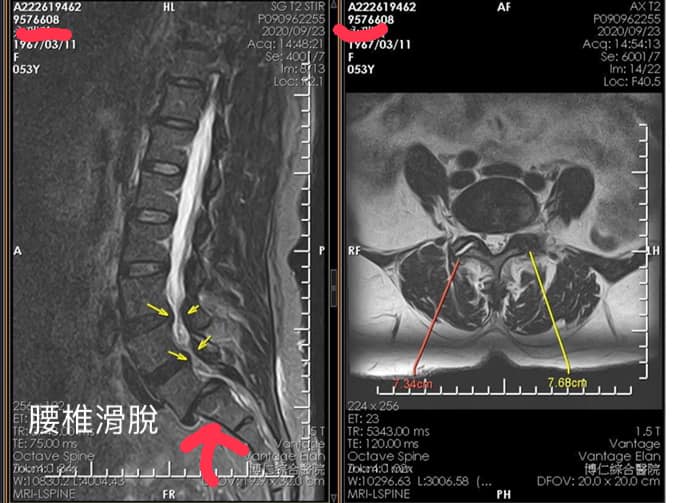

👓前言:端看X光跟MRI會讓人有點嚇一跳,第五腰椎滑脫的很明顯,跟患者說如果治療三週沒改善,可能還是要動刀固定鎖骨釘!

🛑醫案:桃園永小姐抱怨痠痛長達15年左右,最近這半年滑倒2次,一開始只是腰痠痛,後來開始左腳無名指小指明顯麻跟刺痛,在當地中醫做過針灸1個月,也在當地復健科診所做過低週波治療儀半年,晚上睡覺非常疼痛、整天不定時抽痛!最明顯是無法久站超過10分鐘、往前彎洗頭跟洗臉都會誘發腰痛、去當地骨科診所拍片發現明顯滑脫!安排核磁共振也發現椎管狹窄難怪那們痛

1.第五腰椎滑脫(第一度跟第二段中間)

2.L3/L4 , L4/L5椎管輕微狹窄